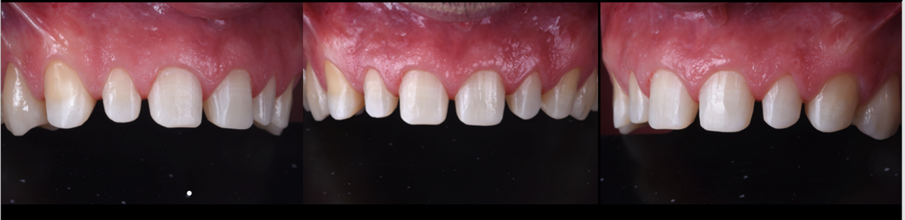

Do naší ordinace přišel 42letý muž, který doufal ve vylepšení svého úsměvu. Byl si vědom opotřebení chrupu v předním úseku a také některých zadních zubů. Tato situace vedla k obnažení značné oblasti dentinu, což způsobilo vysokou citlivost a negativně ovlivnilo estetiku jeho úsměvu (obr. 1). Dále se u něj projevilo určité stěsnání a vztah stoliček III. třídy, což mělo za následek určitou modifikaci okluze, tendenci ke vztahu řezáků III. třídy a skus hrana na hranu (obr. 2).

Obr. 6a, b: Situace před a po ortodontickém ošetření.

Obr. 7a-d: Přímá kompozitní náhrada předního sextantu dolní čelisti.